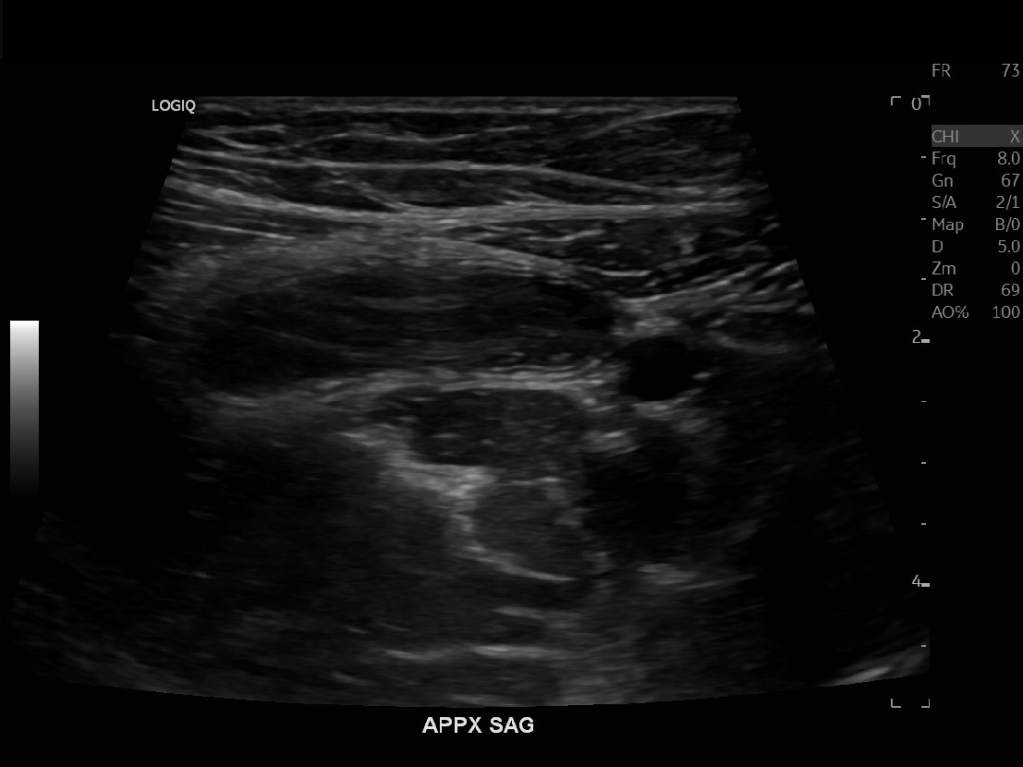

Appendicitis 13

Acute appendicitis @ 1 cm with L2-9mhz and L6-24mhz transducer GE Logiq e10.